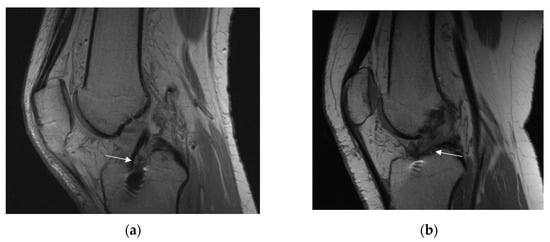

2.1. Measurement on the Sagittal Plane

2.2. Measurement on the Axial Plane

2.4. Indirect Signs of Anterior Cruciate Ligament (ACL) Graft Insufficiency